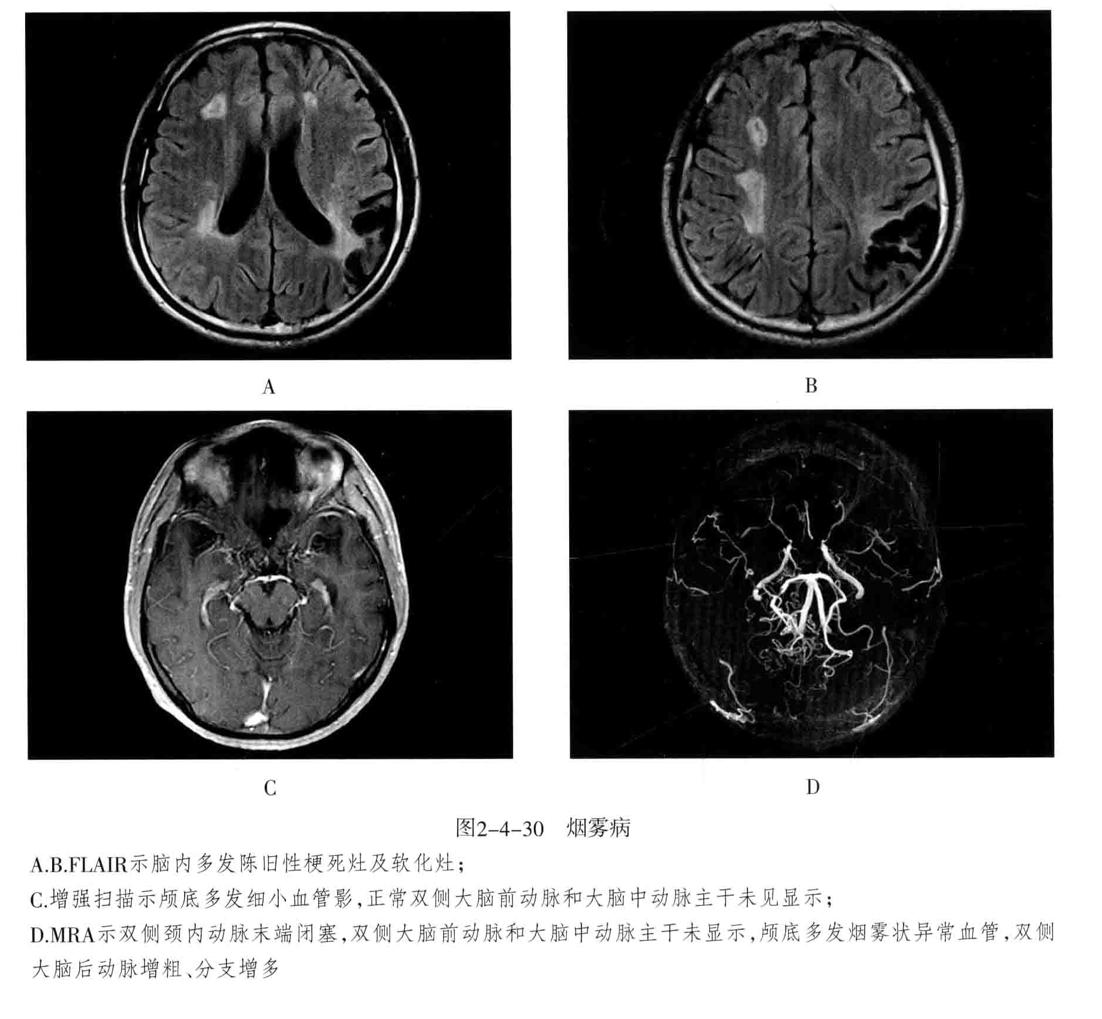

十、烟雾病

又称为脑底异常血管网症、脑底动脉环闭塞症。是以脑内虹吸段至大脑前、中动脉近端狭窄或闭塞,同时伴有广泛侧支循环形成,导致颅底出现异常毛细血管网为特征的脑血管病。好发年龄10岁以下和40-50岁。临床表现为脑缺血和脑出血两大类。儿童多为颈内动脉系统缺血性改变,成人多为颅内出血。

- CT平扫表现为双侧额叶、顶叶及颞叶皮质或皮质下区多发脑梗死及脑萎缩改变,也可以出现颅内出血。增强有时可见到颈内动脉及大脑前中动脉粗细明显不对称,或者充盈不良,甚至不显影。可显示基底池及基底节区的侧支循环网,大多表现为为不规则的扭曲成团的强化血管影。

- MRI表现为脑缺血引起的T1WI低、T2WI高信号脑梗死区,颈内动脉及大脑中动脉主干的“流空效应”变弱或消失,异常血管网在T2WI上表现为基底节区和鞍上池内多发细小血管影,呈网状低信号或无信号区。皮质侧支循环形成时,增强扫描可见皮质血管增多、扩张、强化、呈“常春藤征”。

- MRA可直接显示颈内动脉、大脑前、中动脉狭窄或闭塞,于颅底见烟雾状异常血管网,常可见到颈外动脉和椎-基底动脉分支代偿性增粗。

- 脑血管造影是确诊烟雾病的主要检查方法,可显示狭窄或闭塞的动脉及异常扩张的血管网。